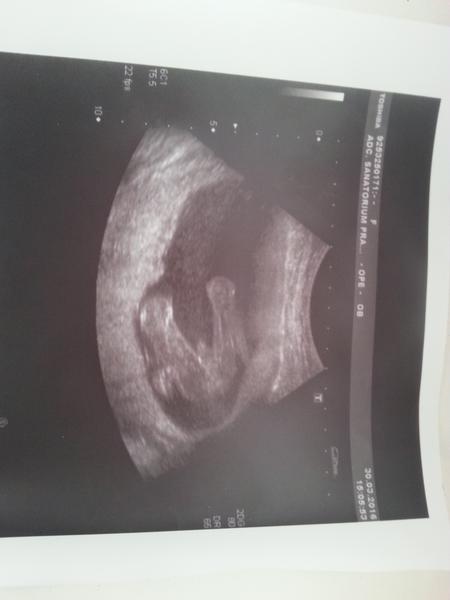

Tak dnes jsme se konečně dozvěděli co čekáme 🙂 Bude to holčička :-*

Holky moc gratuluji k holčičkám , máme potvrzeno ještě z 3D bude to opravdu malý fotbalista 🙂